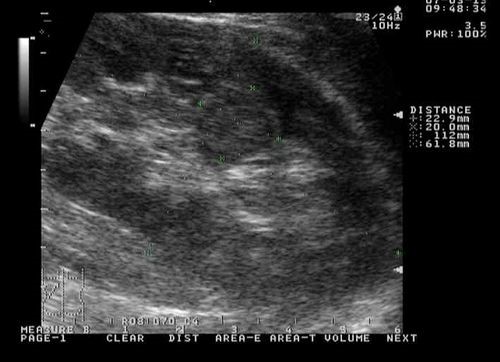

Синусные кисты почек.

Парапельвикальная (окололоханочная) киста. УЗИ через боковой акустический доступ.

Парапельвикальные кисты. УЗИ через боковой акустический доступ.

Самый простой, доступный и эффективный метод обнаружения синусных кист почек – ультразвуковое исследование. Эхография позволяет не только обнаружить кисту почечного синуса маленьких размеров, но и обратить внимание на возможные осложнения в виде сдавления сосудов и лоханки. Существенный недостаток ультразвуковой диагностики – врач-диагност может не выявить мелкое новообразование.